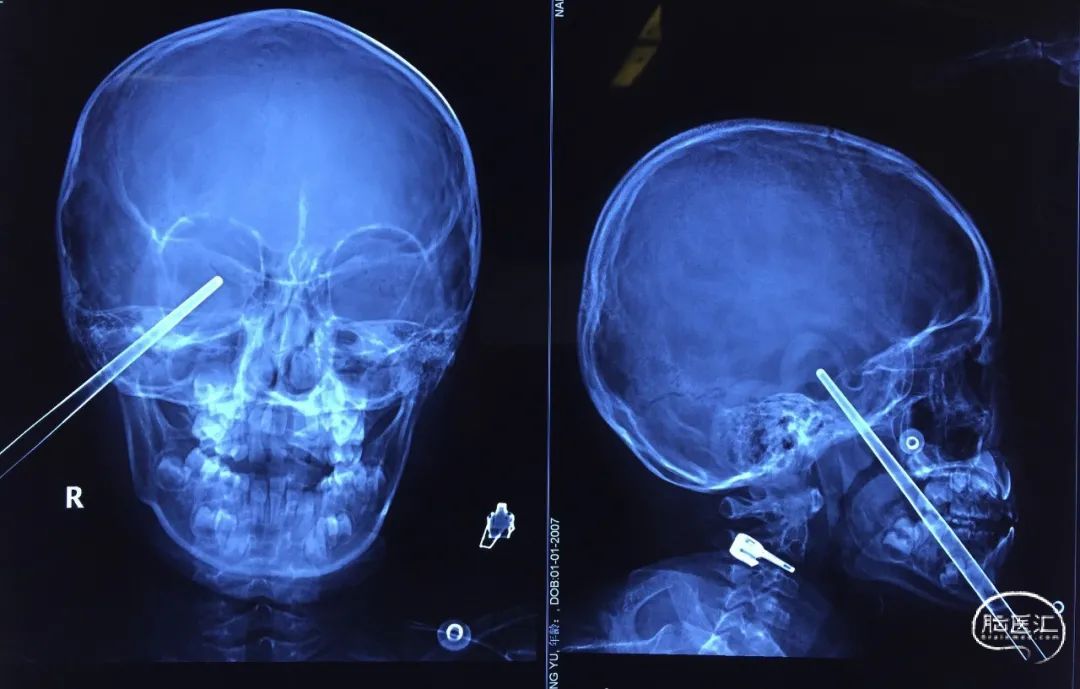

男,42岁,钢筋插入右侧眶部3小时入急诊。

图1. 钢笔自上颌、前颅底贯穿入

图2. 巨大钢筋自下颌,上颌及前颅底贯穿入颅侧位X片

(Ali Erdem Yıldırım, et al. Ulus Travma Acil Cerrahi Derg, 2014)

(张太平,创伤外科杂志,2014)